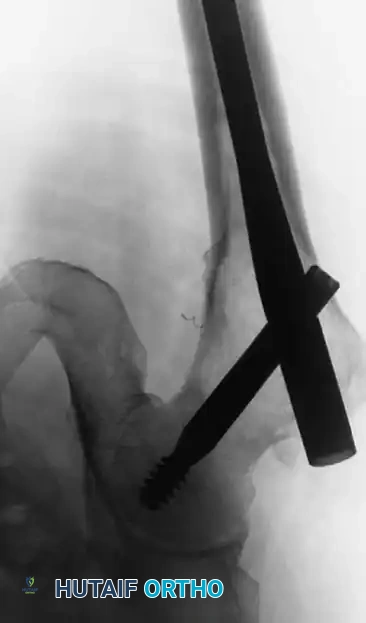

Step-by-Step Surgical Technique: Prophylactic Cephalomedullary Nailing of the Femur

When lymphoma involves the proximal or diaphyseal femur, a long cephalomedullary nail (e.g., Gamma nail) is the implant of choice.

4. Nail Insertion:

* A long cephalomedullary nail is advanced over the guidewire. The nail must span the entire length of the bone to protect against future fractures, especially if the entire femur is to be irradiated.

5. Proximal and Distal Locking:

* Proximal fixation is achieved with a large lag screw directed into the center of the femoral head, providing rotational stability and preventing varus collapse of the proximal femur.

* Distal locking screws are placed via a perfect-circle fluoroscopic technique to secure the distal segment.

Intraoperative anteroposterior fluoroscopic view demonstrating prophylactic fixation of the proximal femur with a long cephalomedullary (Gamma) nail. Note the trajectory of the lag screw into the femoral head.